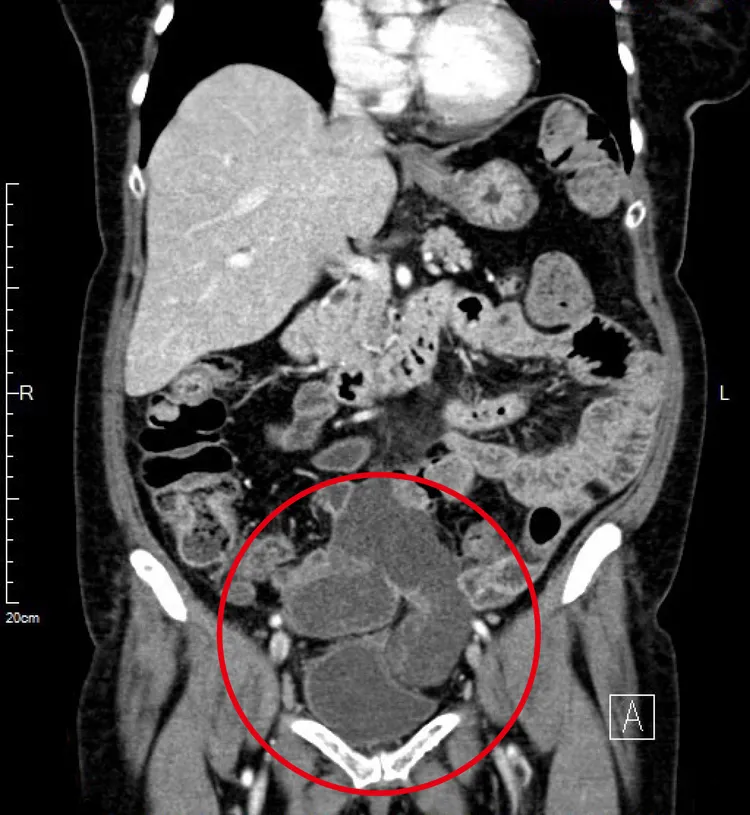

露米的骨盆腔腹膜黏液性腫瘤超過十公分。馬偕提供